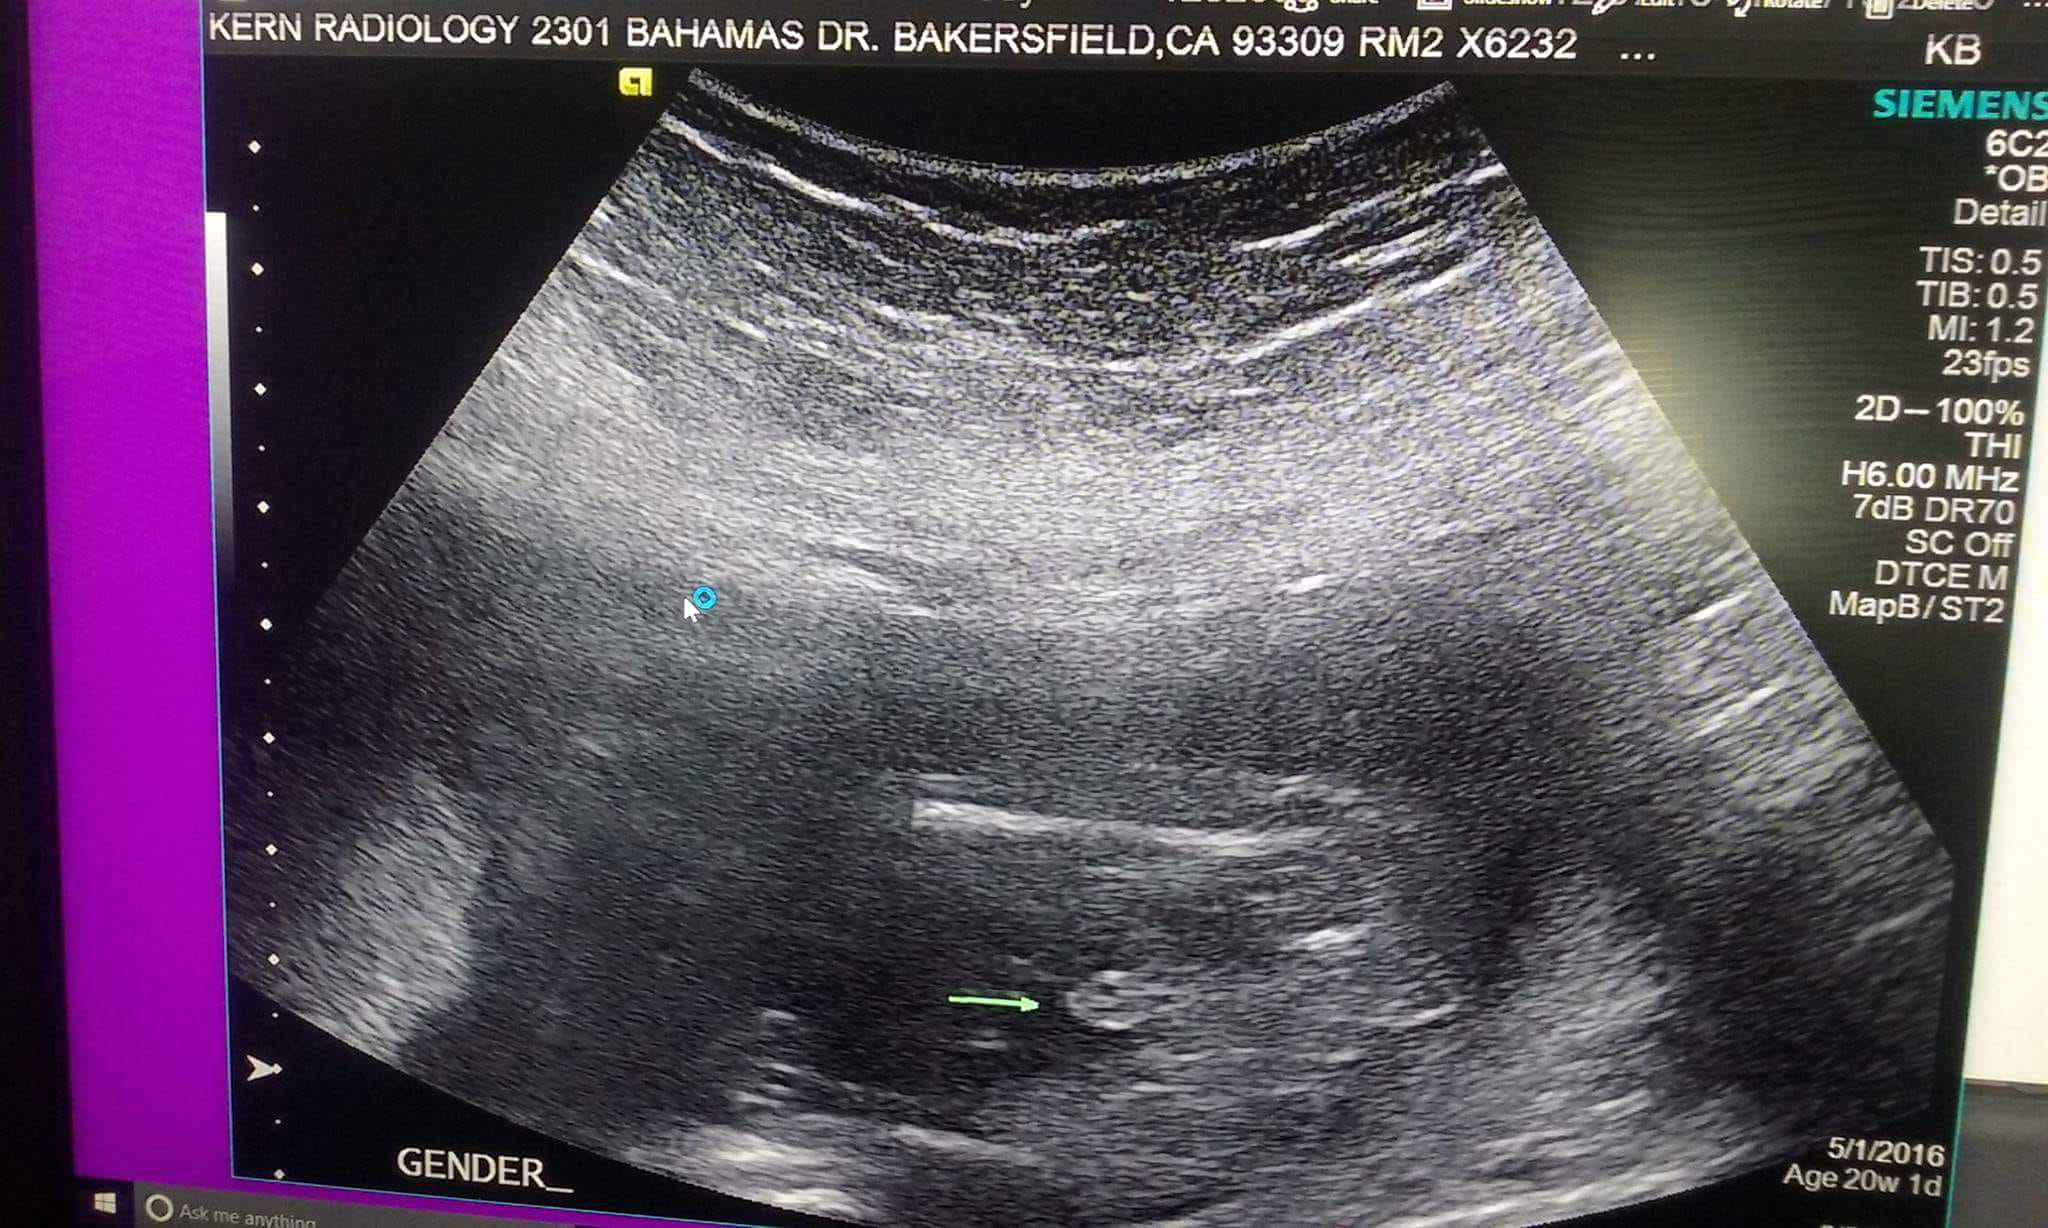

Hola, me hicieron mi ecografia

Y salio el sexo del bebe pero el doctor no me a querido decir el sexo,no entiendo porque,estoy en mi sexto mes de embarazo